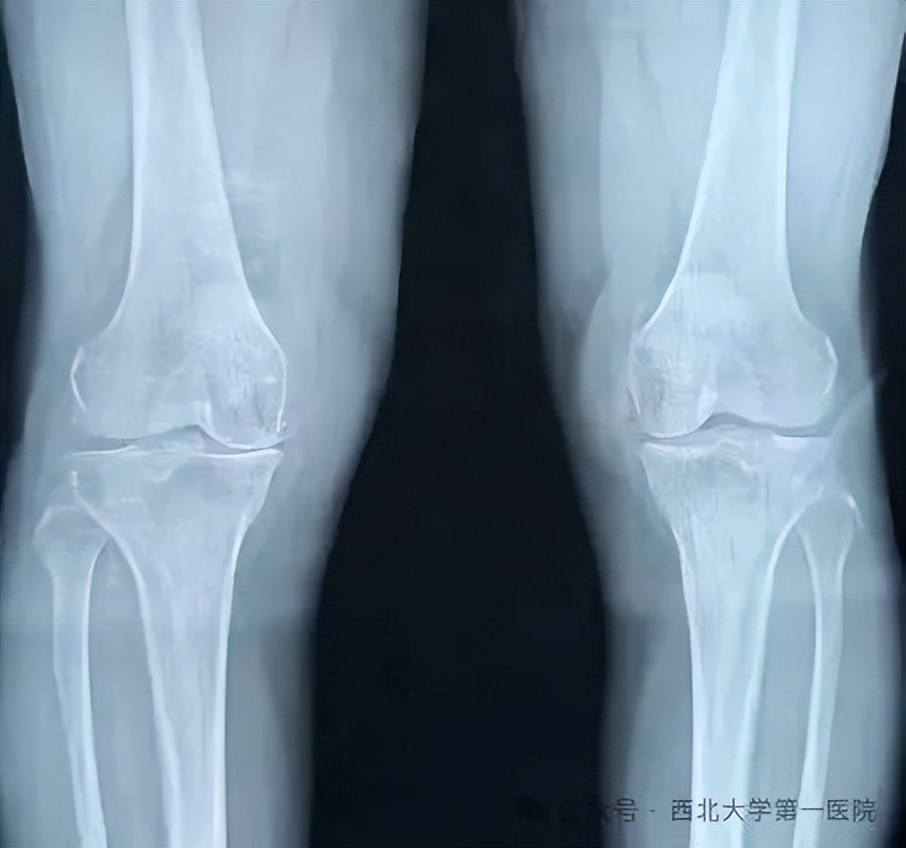

近日,该院骨科一病区再次收治一名膝骨性关节炎的患者,患者为老年男性,术前诊断为右膝内侧间室重度骨关节炎(KL4级),表现为轻度内翻畸形(<15°)和典型的膝关节内侧“拇指痛”。影像学检查显示其内侧间室已呈“骨对骨”的晚期磨损表现,髌上囊巨大游离体。

术后即刻行膝关节正侧位,显示假体大小、位置等均良好。